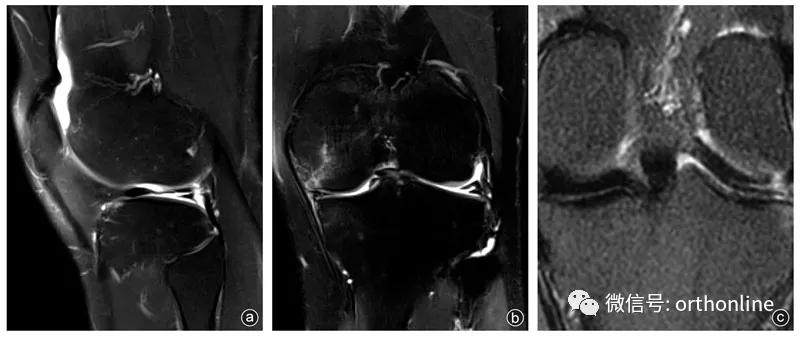

病人,男,19岁,左膝关节时常有伸屈活动时弹响,入院3周前军事训练时扭伤左膝关节,后出现肿胀,频繁出现关节绞锁、弹响并伴有疼痛。查体:左膝关节过屈过伸痛(+),外侧关节间隙压痛,麦氏征(+),左膝关节MRI提示外侧盘状半月板并水平分层撕裂(图1)。行关节镜下检查见半月板桶柄样撕裂并嵌顿于股骨髁间,外侧半月板为 Wrisberg 韧带型(图2 a-c),行盘状半月板成形,半月板后角胫骨止点重建固定,并将游离缘缝合固定于关节囊(图2 d-j)。术后1年复查MRI显示半月板愈合良好,左膝关节疼痛、弹响及绞锁症状消失(图2 k-l)。

图1

图1 病人术前MRI影像学资料 a:术前矢状位MRI显示半月板体部及后角撕裂;b:术前冠状位MRI显示半月板水平撕裂;c:术前外侧半月板后根部冠状位MRI显示外侧半月板后根部与胫骨、关节囊无附着,呈Wrisberg韧带